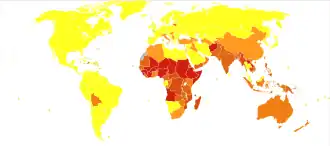

Rabies causes about 59,000 deaths worldwide per year,[6] about 40% of which are in children under the age of 15.[16] More than 95% of human deaths from rabies occur in Africa and Asia.[1] Rabies is present in more than 150 countries and on all continents but Antarctica.[1] More than 3 billion people live in regions of the world where rabies occurs.[1] A number of countries, including Australia and Japan, as well as much of Western Europe, do not have rabies among dogs.[17][18] Many Pacific islands do not have rabies at all.[18] It is classified as a neglected tropical disease.[19]

In 2010, an estimated 26,000 people died from rabies, down from 54,000 in 1990.[101] The majority of the deaths occurred in Asia and Africa.[100] As of 2015, India (approximately 20,847), followed by China (approximately 6,000) and the Democratic Republic of the Congo (5,600), had the most cases.[102] A 2015 collaboration between the World Health Organization, World Organization of Animal Health (OIE), Food and Agriculture Organization of the United Nation (FAO), and Global Alliance for Rabies Control has a goal of eliminating deaths from rabies by 2030.[103]